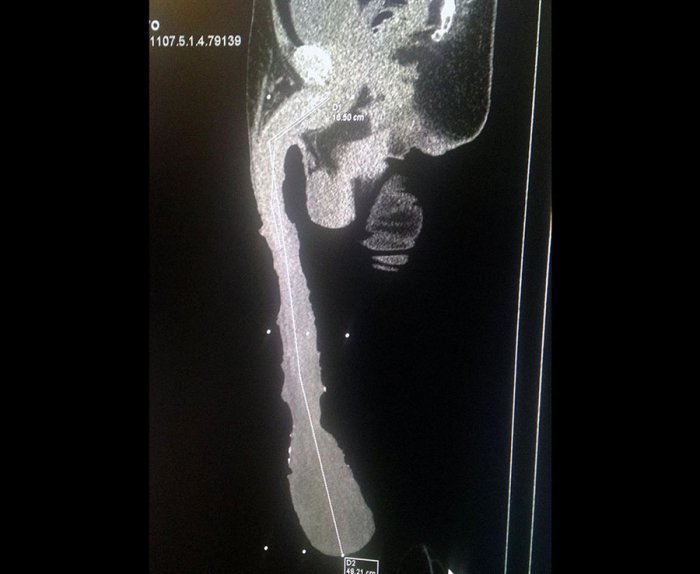

54-летний мексиканец Роберто Эскивел Кабрера – обладатель самого большого пениса на планете. Среди людей, разумеется. Длина его хозяйства – 48 сантиметров. Рекорд этот зафиксирован еще в 2015 году, однако в Книгу Рекордов Гиннеса пока не попал, там всё еще американский актер Джона Фалкон с его жалкими 33 сантиметрами.

Чувствует себя он скорее плохо. Огромный размер пениса – побочный результат какого-то странного недуга, так как у него не только размер необычный, но и форма. Что полностью исключает сексуальные контакты. Врачи утверждают, что в молодости мистер Кабрера наверняка пытался увеличить размер мужского достоинства при помощи грузиков, однако перестарался, что в результате вызвало эффект снежного кома, когда пенис начал растягиваться под собственным весом уже без дополнительного груза, отекать и менять форму. В результате во взрослом возрасте мужчина предпринимал попытки заняться сексом, но по техническим причинам ничего не вышло. Сейчас мечтает накопить денег чтобы попробовать перенести операцию по уменьшению пениса, но врачи прогнозов пока дать не могут.